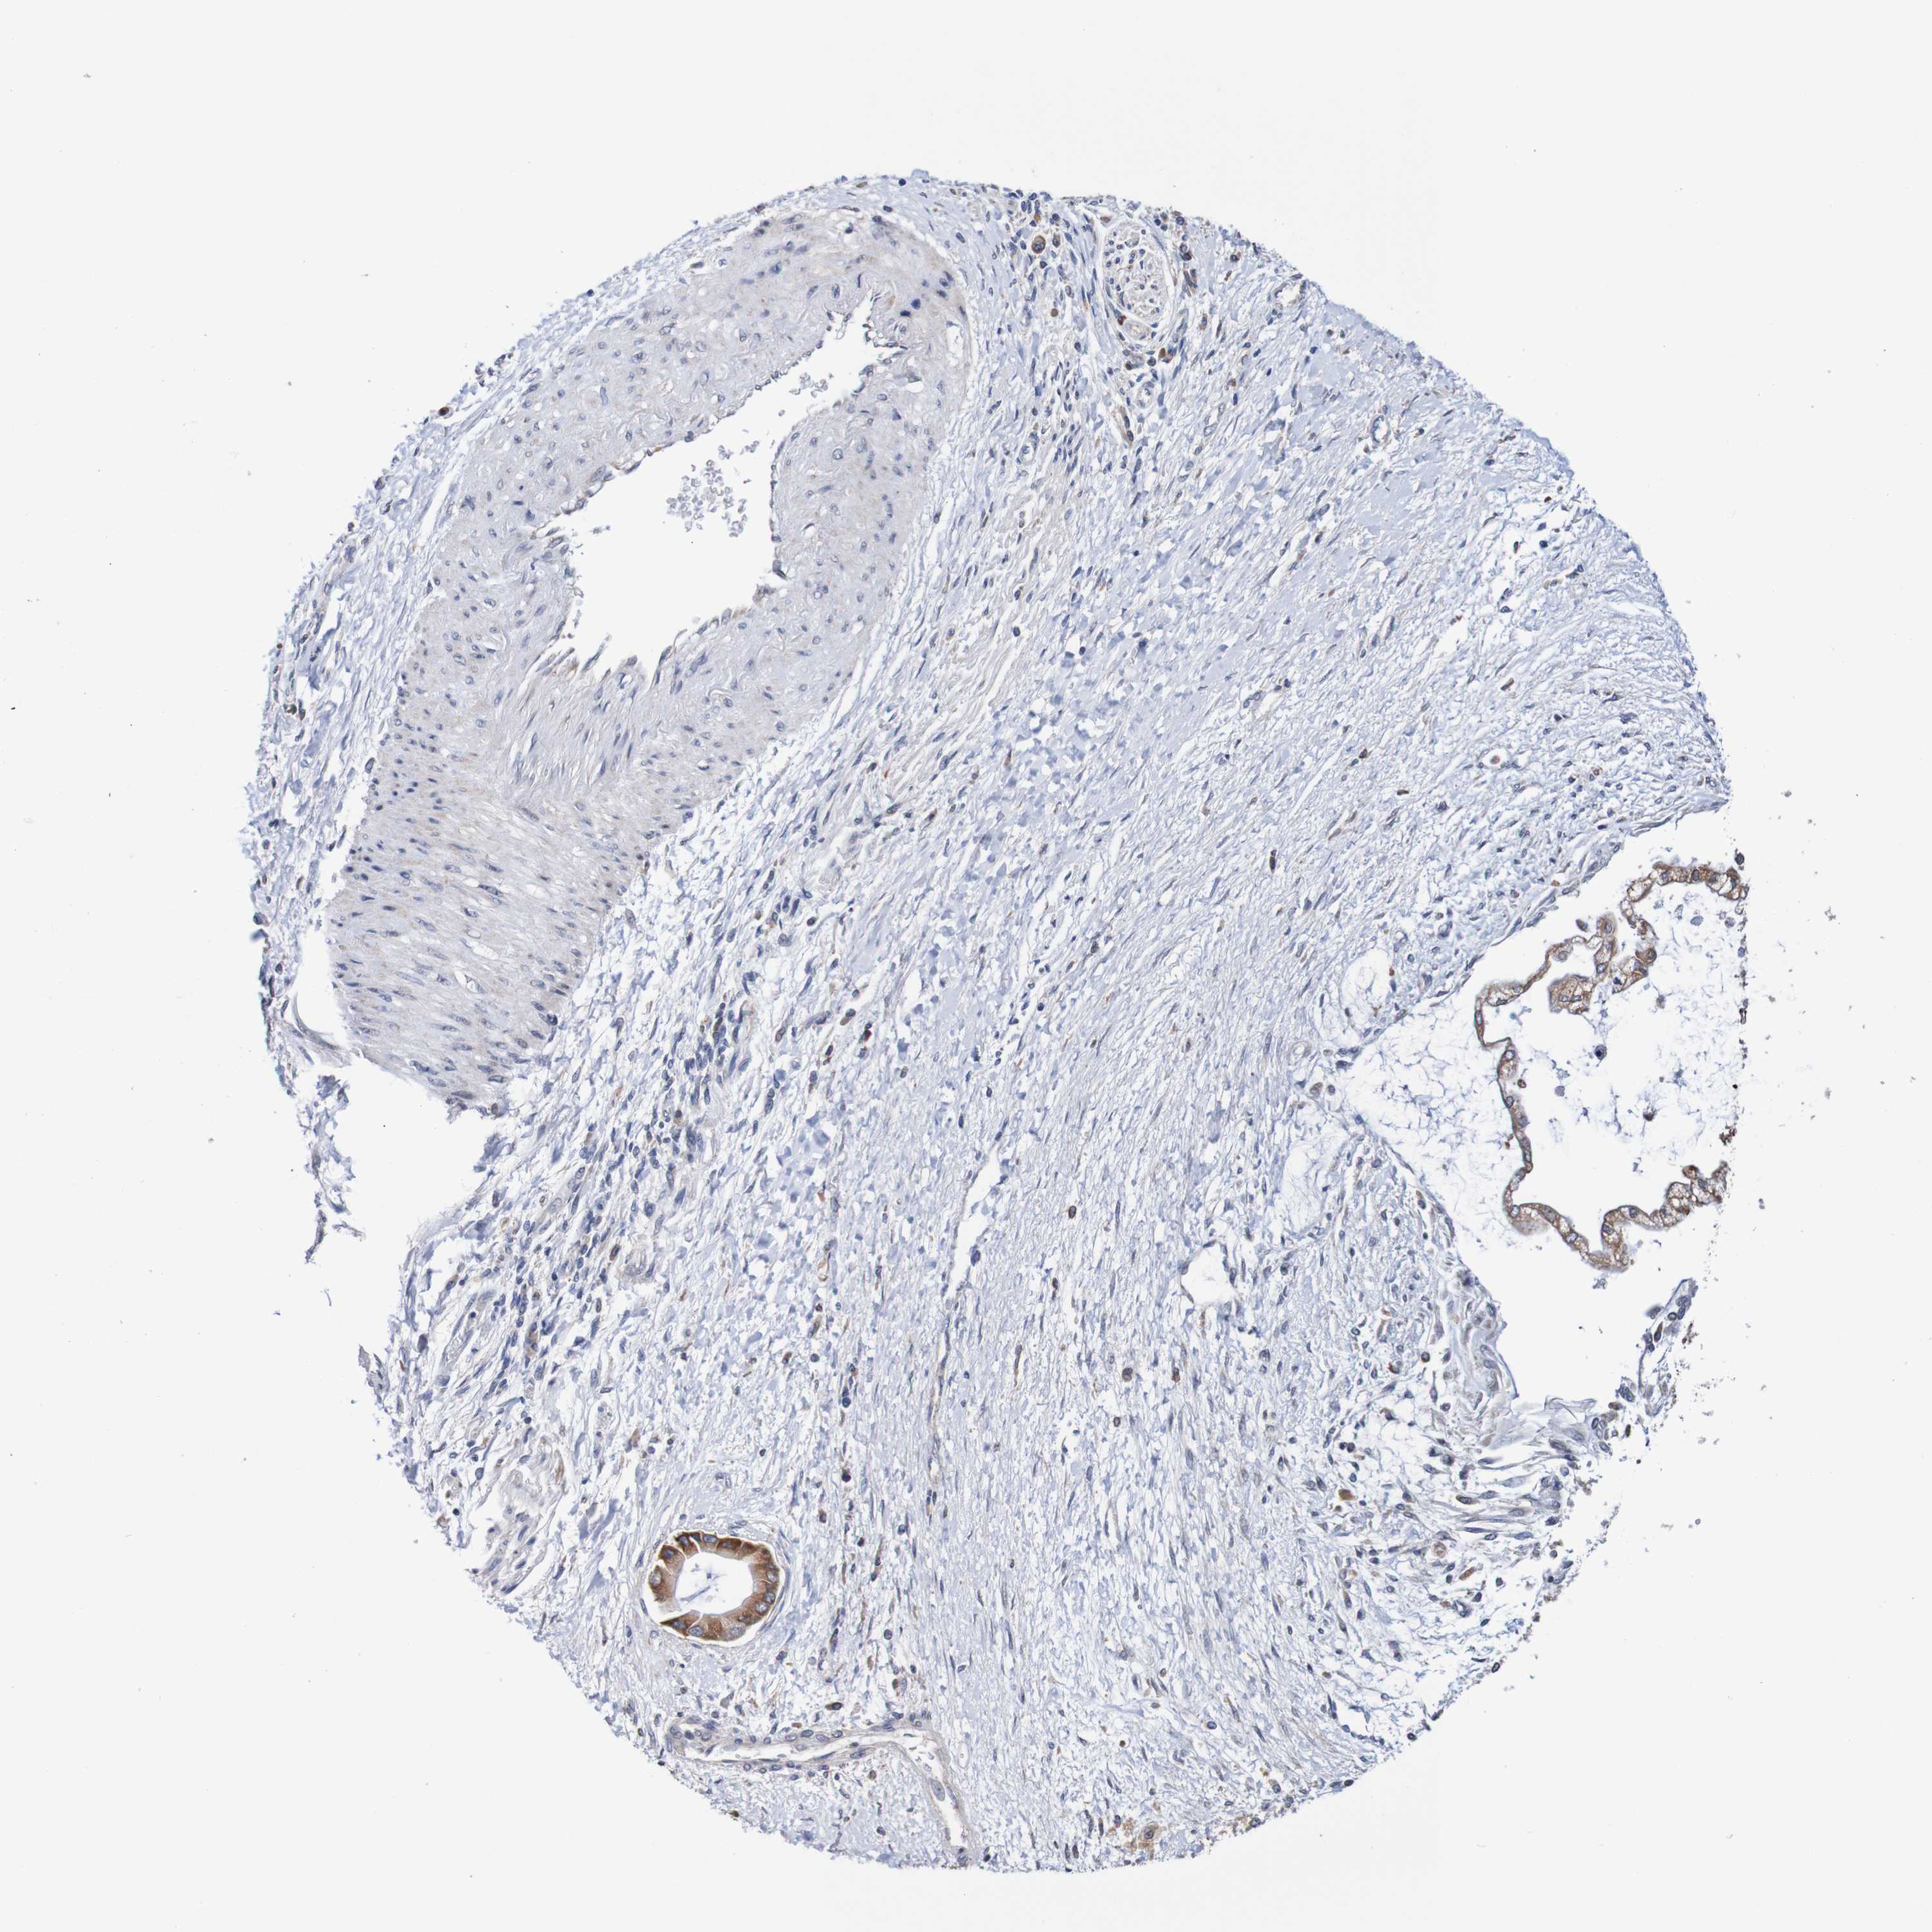

LIVER CANCER - Protein expressioni

A mouse-over function shows sample information and annotation data. Click on an image to view it in a full screen mode. Samples can be filtered based on level of antibody staining by selecting one or several of the following categories: high, medium, low and not detected. The assay and annotation is described here.

Antibody stainingi

Antibody staining in the annotated cell types in the current human tissue is reported as not detected, low, medium, or high, based on conventional immunohistochemistry profiling in selected tissues. This score is based on the combination of the staining intensity and fraction of stained cells.

Each image is clickable and will lead to virtual microscopy that enables deeper exploration of all samples and also displays staining intensity scores, fraction scores and subcellular localization as well as patient and tissue information for each sample.

Antibody HPA011729

Staining

High

Medium

Low

Not detected

Intensity

Strong

Moderate

Weak

Negative

Quantity

>75%

75%-25%

<25%

None

Location

Nuclear

Cytoplasmic/membranous

Cytoplasmic/membranous,nuclear

Cholangiocarcinoma

Carcinoma, Hepatocellular, NOS